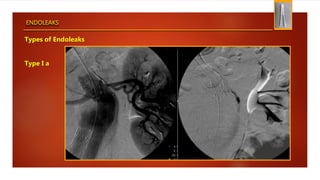

Type I a

ENDOLEAKS

Types of Endoleaks